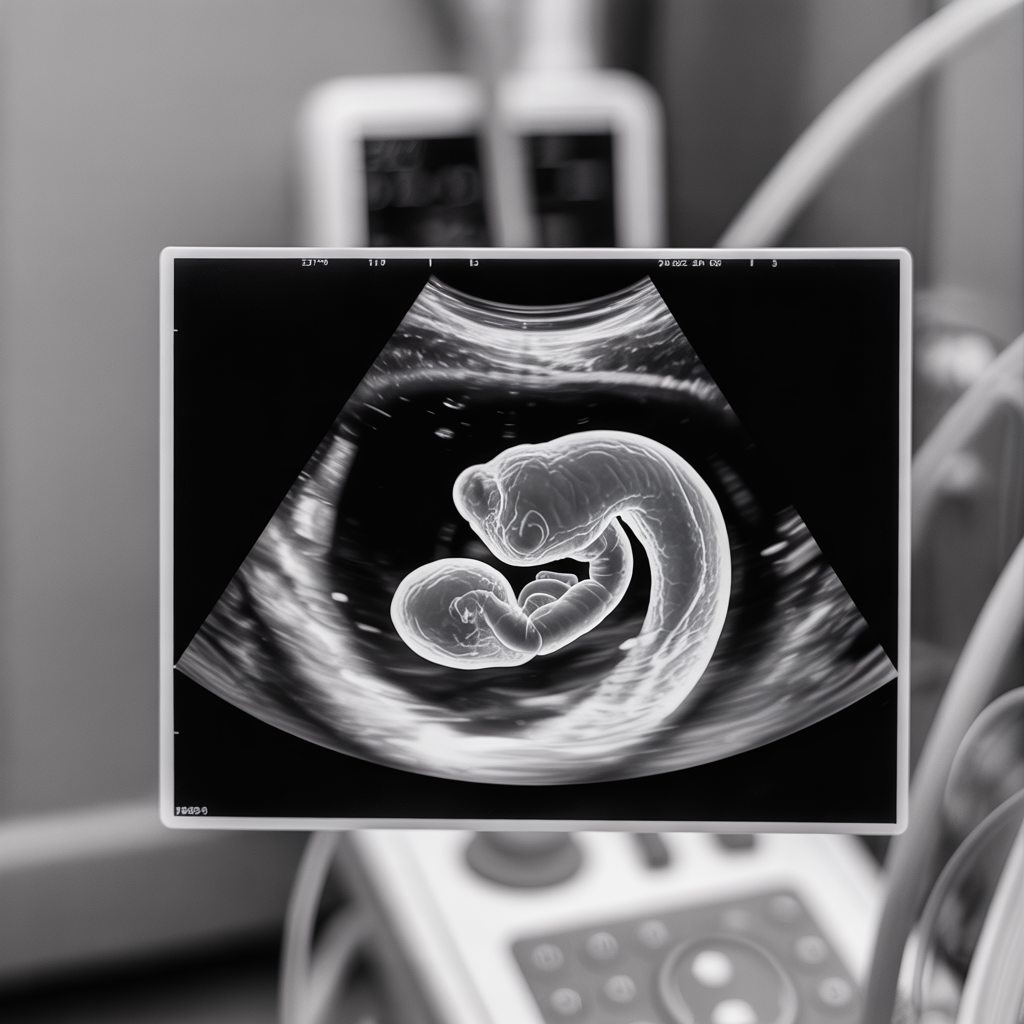

תקופת ההיריון מהווה מסע מופלא של התפתחות ושינויים הן עבור האם והן עבור העובר המתפתח ברחמה. במהלך תשעה חודשים, תא בודד הופך לתינוק שלם עם מערכות גוף מורכבות. הבנת התהליכים המתרחשים בכל שליש של ההיריון יכולה לסייע לך להתכונן טוב יותר לשינויים הצפויים ולחוות את ההיריון בצורה מודעת ורגועה יותר. במאמר זה נסקור את השינויים …

התפתחות העובר: מה קורה בכל שליש להריון? מידע שמעניין לדעת לקריאה »